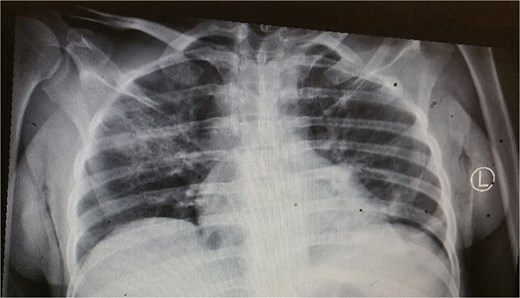

The patient had a normal white cell count of 4600/mm3, but the hemoglobin level was low at 5.8 g/dl. The serum electrolytes, renal function, and liver function tests were all within the normal range. Chest X-ray showed right lung consolidation (Fig. 1). No free air was seen under the diaphragm.